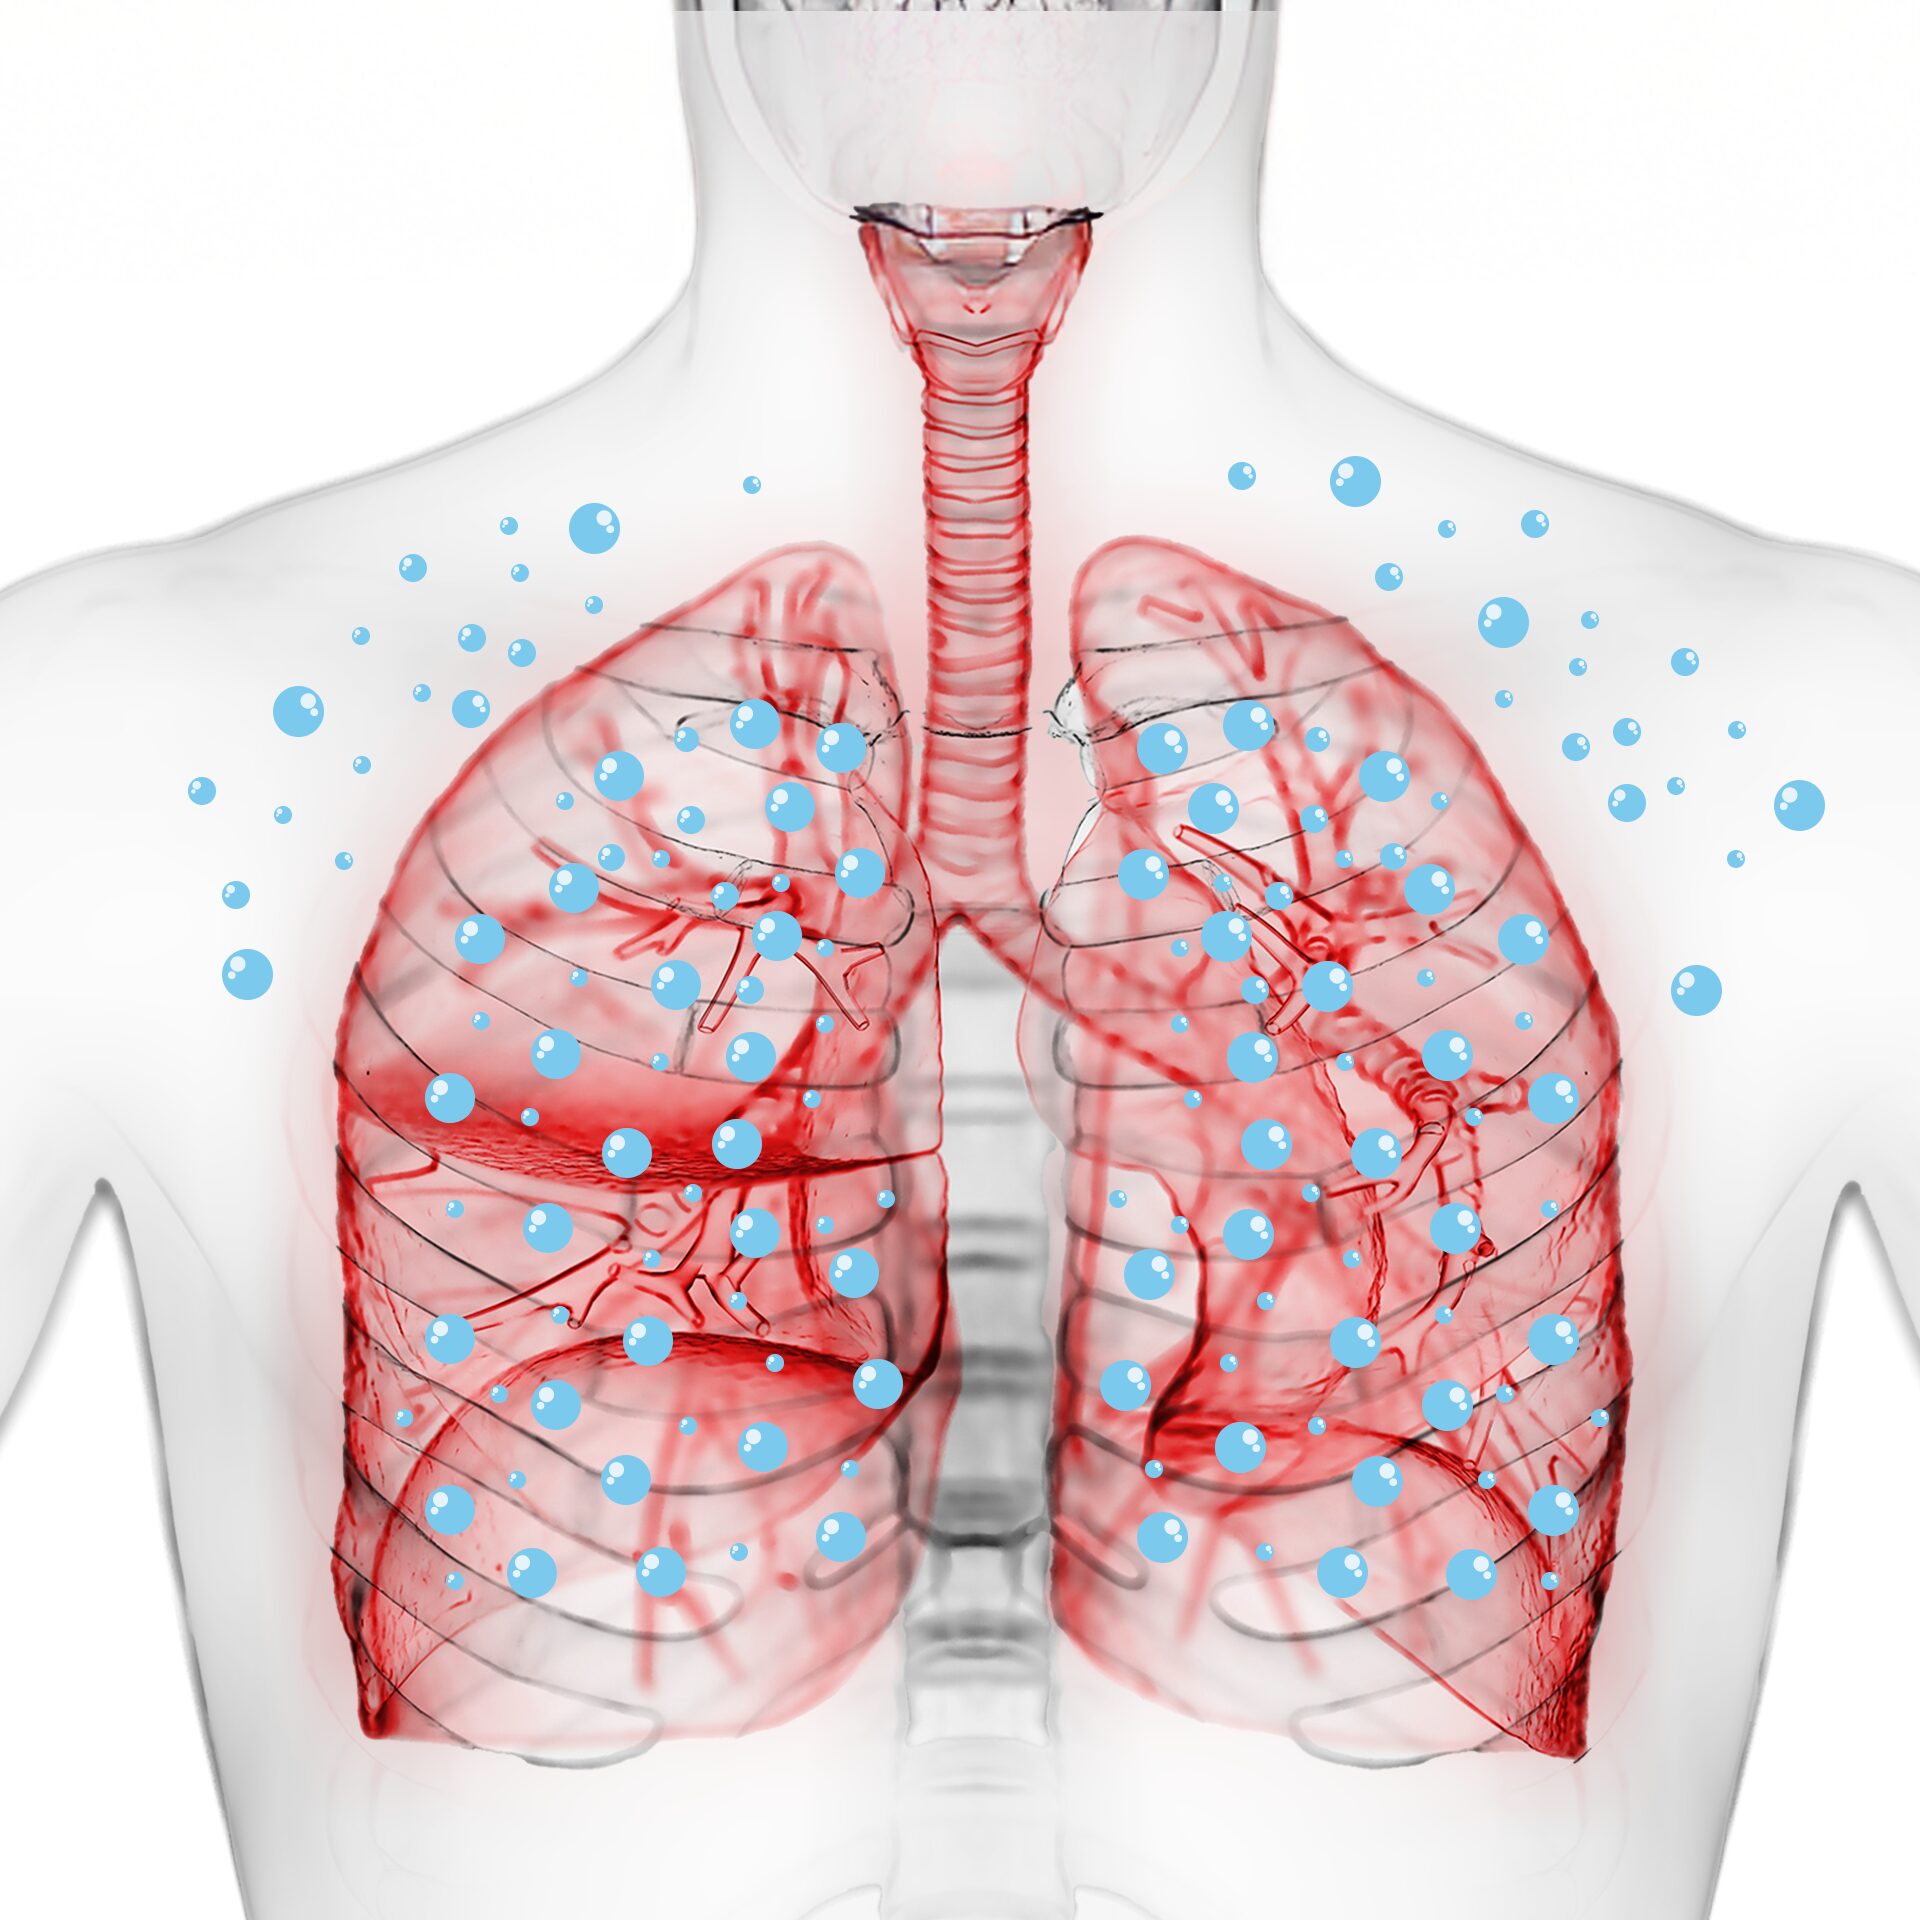

고압산소 치료란 ?

고압산소 항노화 치료는 대기압보다 높은 2기압을 인위적으로 만들어

챔버 안에서 환자가 100% 순도의 산소를 마시는 치료 방법입니다.

기존보다 2배의 산소가 혈액에 반응하여

손상된 조직이나 세포를 케어하는 최첨단 전신 항노화 치료 입니다.